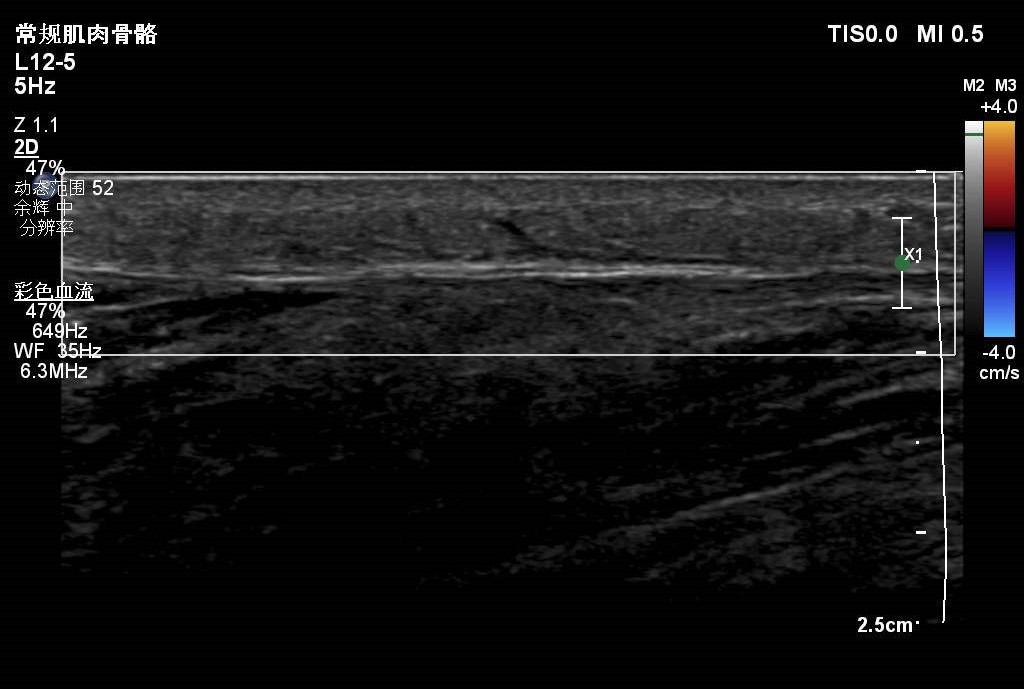

患者大腿远端浅表可见一包块隆起,自述半月前出现红肿,目前未见明显红肿,触摸感觉微痛。

根据病情考虑可能蚊虫叮咬水肿。大家考虑是什么?有没有专家给看看,是什么?谢谢。